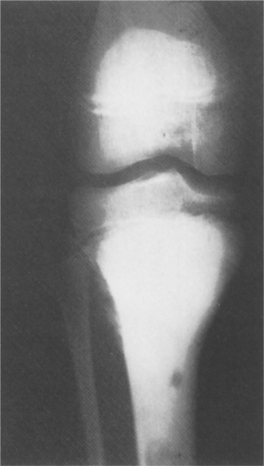

Osteosarcoma seems to appear in bones undergoing an active growth phase and appears at the epiphyseal plate of rapidly growing bone in adolescents. The long bones such as the distal femur, proximal humerus, and proximal tibia have a relatively more active growth period than other bones, which makes them more vulnerable (Fig. 26-6).

Figure 26-6 Osteosarcoma. An extremely sclerotic lesion in the proximal tibia of a child is noted, which is characteristic of an osteogenic sarcoma. (From Helms C: Fundamentals of skeletal radiology: benign cystic lesions, Philadelphia, 1989, WB Saunders.)